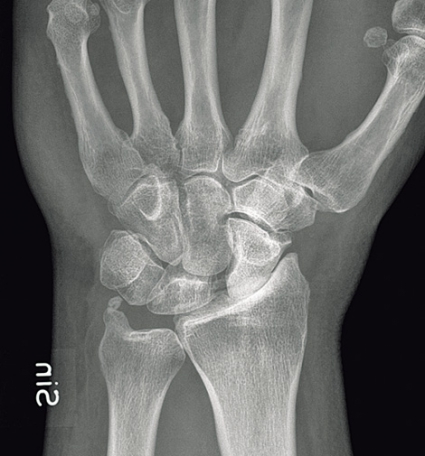

Vi redogör här förenklat för perilunära luxationer och transskafoidala perilunära luxationer. Skadorna består av »lesser arc injuries«, dvs isolerade perilunära ligamentskador, och »greater arc injuries«, dvs där det föreligger samtidiga frakturer av karpalben och/eller styloider. Dessa skador är alltid högenergiskador [9], som t ex trafikolyckor eller fall från hög höjd. De drabbar främst yngre män och utgör ca 7 procent av alla akuta karpala skador.

Ungefär 10 procent av skadorna är öppna. Svårighetsgraden av framför allt de slutna skadorna undervärderas ofta. Så mycket som en femtedel av skadorna missas ofta primärt. Symtom och fynd vid akuta skador är felställning i handleden, som dock lätt kan döljas av svullnaden. Dessutom är rörelseförmågan i handleden nedsatt liksom ibland även fingerrörligheten. Smärtan behöver inte vara uttalad, vilket bidrar till att denna komplicerade skada ibland kan missas akut.

Observera att samtidiga ipsilaterala skador, t ex armbågsluxation, är vanliga. Akut karpaltunnelsyndrom förekommer i ungefär en tredjedel av fallen. Diagnosen ställs på röntgenbilden: Leta efter oordning bland karpalbenen och brutna Gilulas linjer! Observera att luxationen främst framträder på sidobilden, medan frontalbilden kan förefalla närmast normal. Man ska vara frikostig med datortomografi (DT), som kan påvisa mer ovanliga skademönster och synliggöra associerade karpala frakturer. Scaphoideum- och capitatum-frakturer är i detta sammanhang vanligast förekommande. DT kan också underlätta valet av snittföring. Observera att dessa skador alltid kräver öppen kirurgi, även om primär reposition lyckas och kontrollröntgen inte visar några frakturer. Enbart perkutan stiftfixation är aldrig till fyllest.